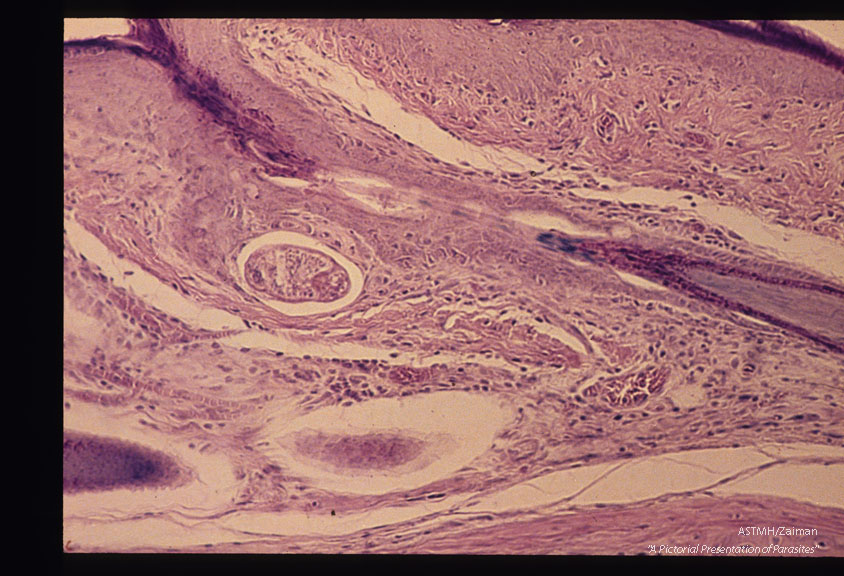

Most common migratory path is between the malpighian layer and the dermis.

Description: Most common migratory path is between the malpighian layer and the dermis.